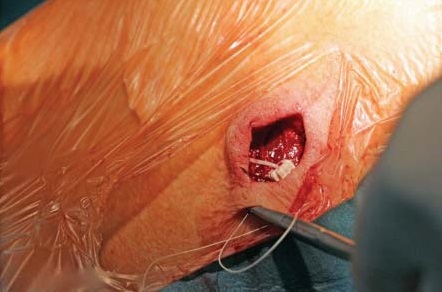

Методика имплантации. Пациенту выполнена люмбальная пункция в проекции L1-сегмента иглой Туохи парамедианным доступом. Интратекально в краниальном направлении заведен спинальный катетер на 6 см. Проведена морфиновая проба (в субарахноидальное пространство введено 100 мкг морфина). Через несколько минут пациент отметил уменьшение болевого синдрома по НОШ с 80 до 10%. На этом фоне пациент смог безболезненно повернуться на спину. Морфиновая проба рассмотрена как положительная, имплантирована порт-система «B|Braun Celsitest 304-20». Камера порта выведена подкожно по передней подмышечной линии в проекции пятого межреберья. Последовательность ключевых этапов манипуляции представлена на рисунках 1–8.

Рис. 7. Камера порт-системы имплантированная в заранее сформированный подкожный карман